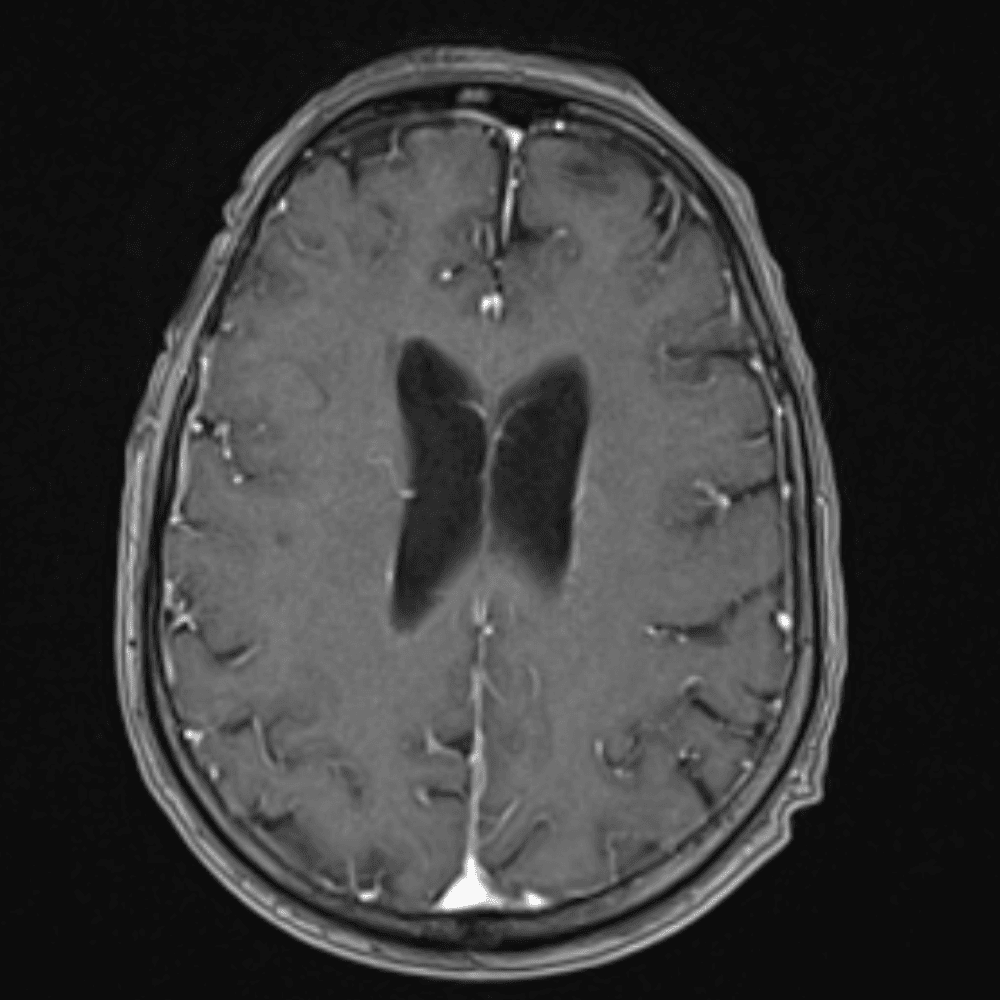

๋‹น์ง ์‹œ ํ”ํžˆ ๋ณผ ์ˆ˜ ์žˆ๋Š” ์‚ฌ๋ก€์˜ ์ „ํ˜•์ ์ธ ์˜ˆ๋ฅผ ํฌํ•จํ•ฉ๋‹ˆ๋‹ค.

39 ์‚ฌ๋ก€

์—ฐ์Šต

๋ฏธ๋ฌ˜ํ•˜๊ฑฐ๋‚˜ ์–ด๋ ค์šด ์‚ฌ๋ก€์™€ ์ผ๋ถ€ ์ •์ƒ ์‚ฌ๋ก€๋ฅผ ํฌํ•จํ•˜์—ฌ ๋‹น์ง์„ ์‹œ๋ฎฌ๋ ˆ์ด์…˜ํ•ฉ๋‹ˆ๋‹ค.

50 ์‚ฌ๋ก€